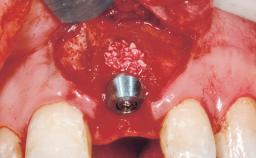

Bone Augmentation Horizontal|Simultaneous

Augmentation Materials Autogenous chips|Xenogenous|Membrane

Bone Volume Deficient horizontally, allowing simultaneous augumentation